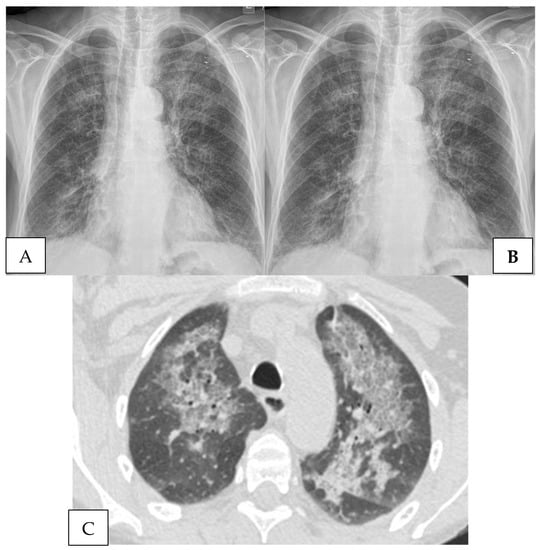

4.2. Radiography